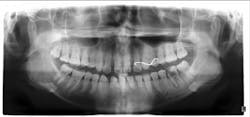

On the other hand, we sometimes spot a huge lesion (with or without digital help) when the patient has no symptoms ("Hey, Doc, it's not bothering me so why worry?"), and we go in with trepidation hoping to avoid an exposure or go right into endo.